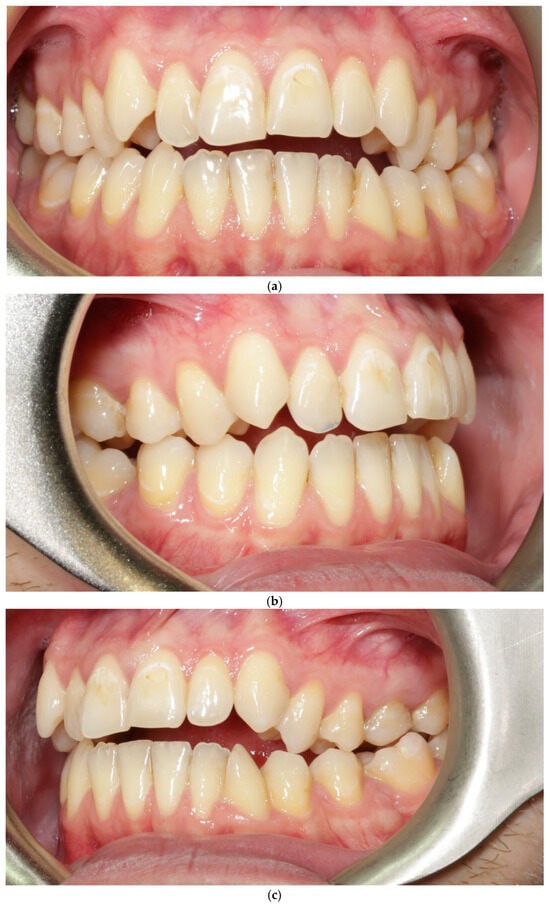

3.2. Patient 2—Soft-Tissue and Intra-Arch Control Outcomes

Because BPS was applied only in the maxillary arch, this patient provided an intra-arch control model under identical biological conditions. The maxillary BPS arch appeared to show features consistent with thickening of the vestibular phenotype, increased soft-tissue resilience, and reduced root translucency. In contrast, the mandibular control arch (treated with conventional biomechanics) appeared to retain a thin, translucent, and flattened phenotype. These qualitative clinical observations from both patients and both arches, including the intra-arch control, are summarized in Table 1.

Gingival phenotype was assessed using a standardized periodontal probe transparency test and evaluation of tissue resistance. No recession, pathological probing depths, or BOP were recorded. Although no ultrasonographic or transgingival thickness measurements were collected, the photographic changes were reproducible and consistent with recognized clinical indicators of phenotype thickening.

No adverse periodontal events were observed (Figure 5a–c). All changes in soft-tissue phenotype in the BPS arch occurred without any surgical augmentation.

Figure 5.

Patient 2 after expansion and BPS removal from the upper arch under treatment (a–c).